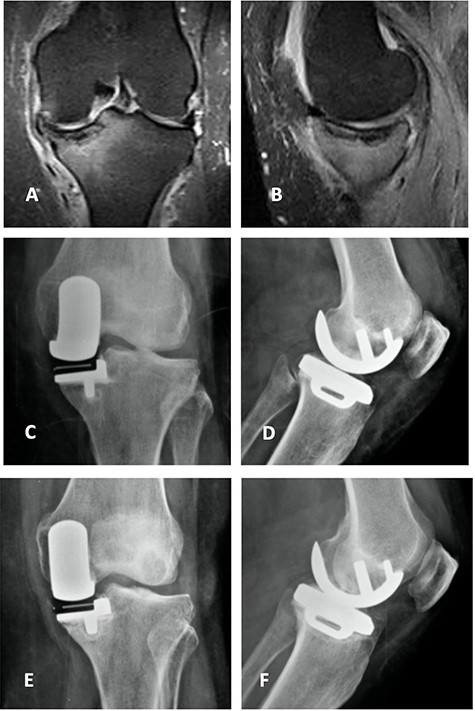

Left knee T2 coronal MRI (top left) showing MP and femoral condyle SIFK with articular failure of both surfaces; Top right: same image (T1); Bottom left: orthostatic anterior view X-ray image of the same patient showing medial compartment bone-on-bone contact; Bottom right: lateral view X-ray image of the same patient.